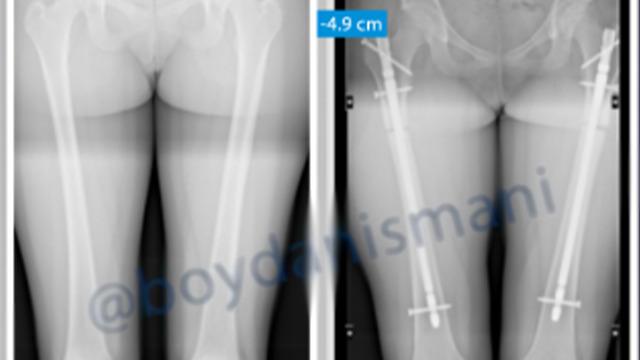

Akın akın Türkiye'ye geliyorlar! Yeni moda boy kısaltma ameliyatı... Cerrahi paket bile yapmışlar: Ameliyat olana şehir gezisi, restoran turları ve tekne turu...

27-08-25 09:03

boy

ameliyat